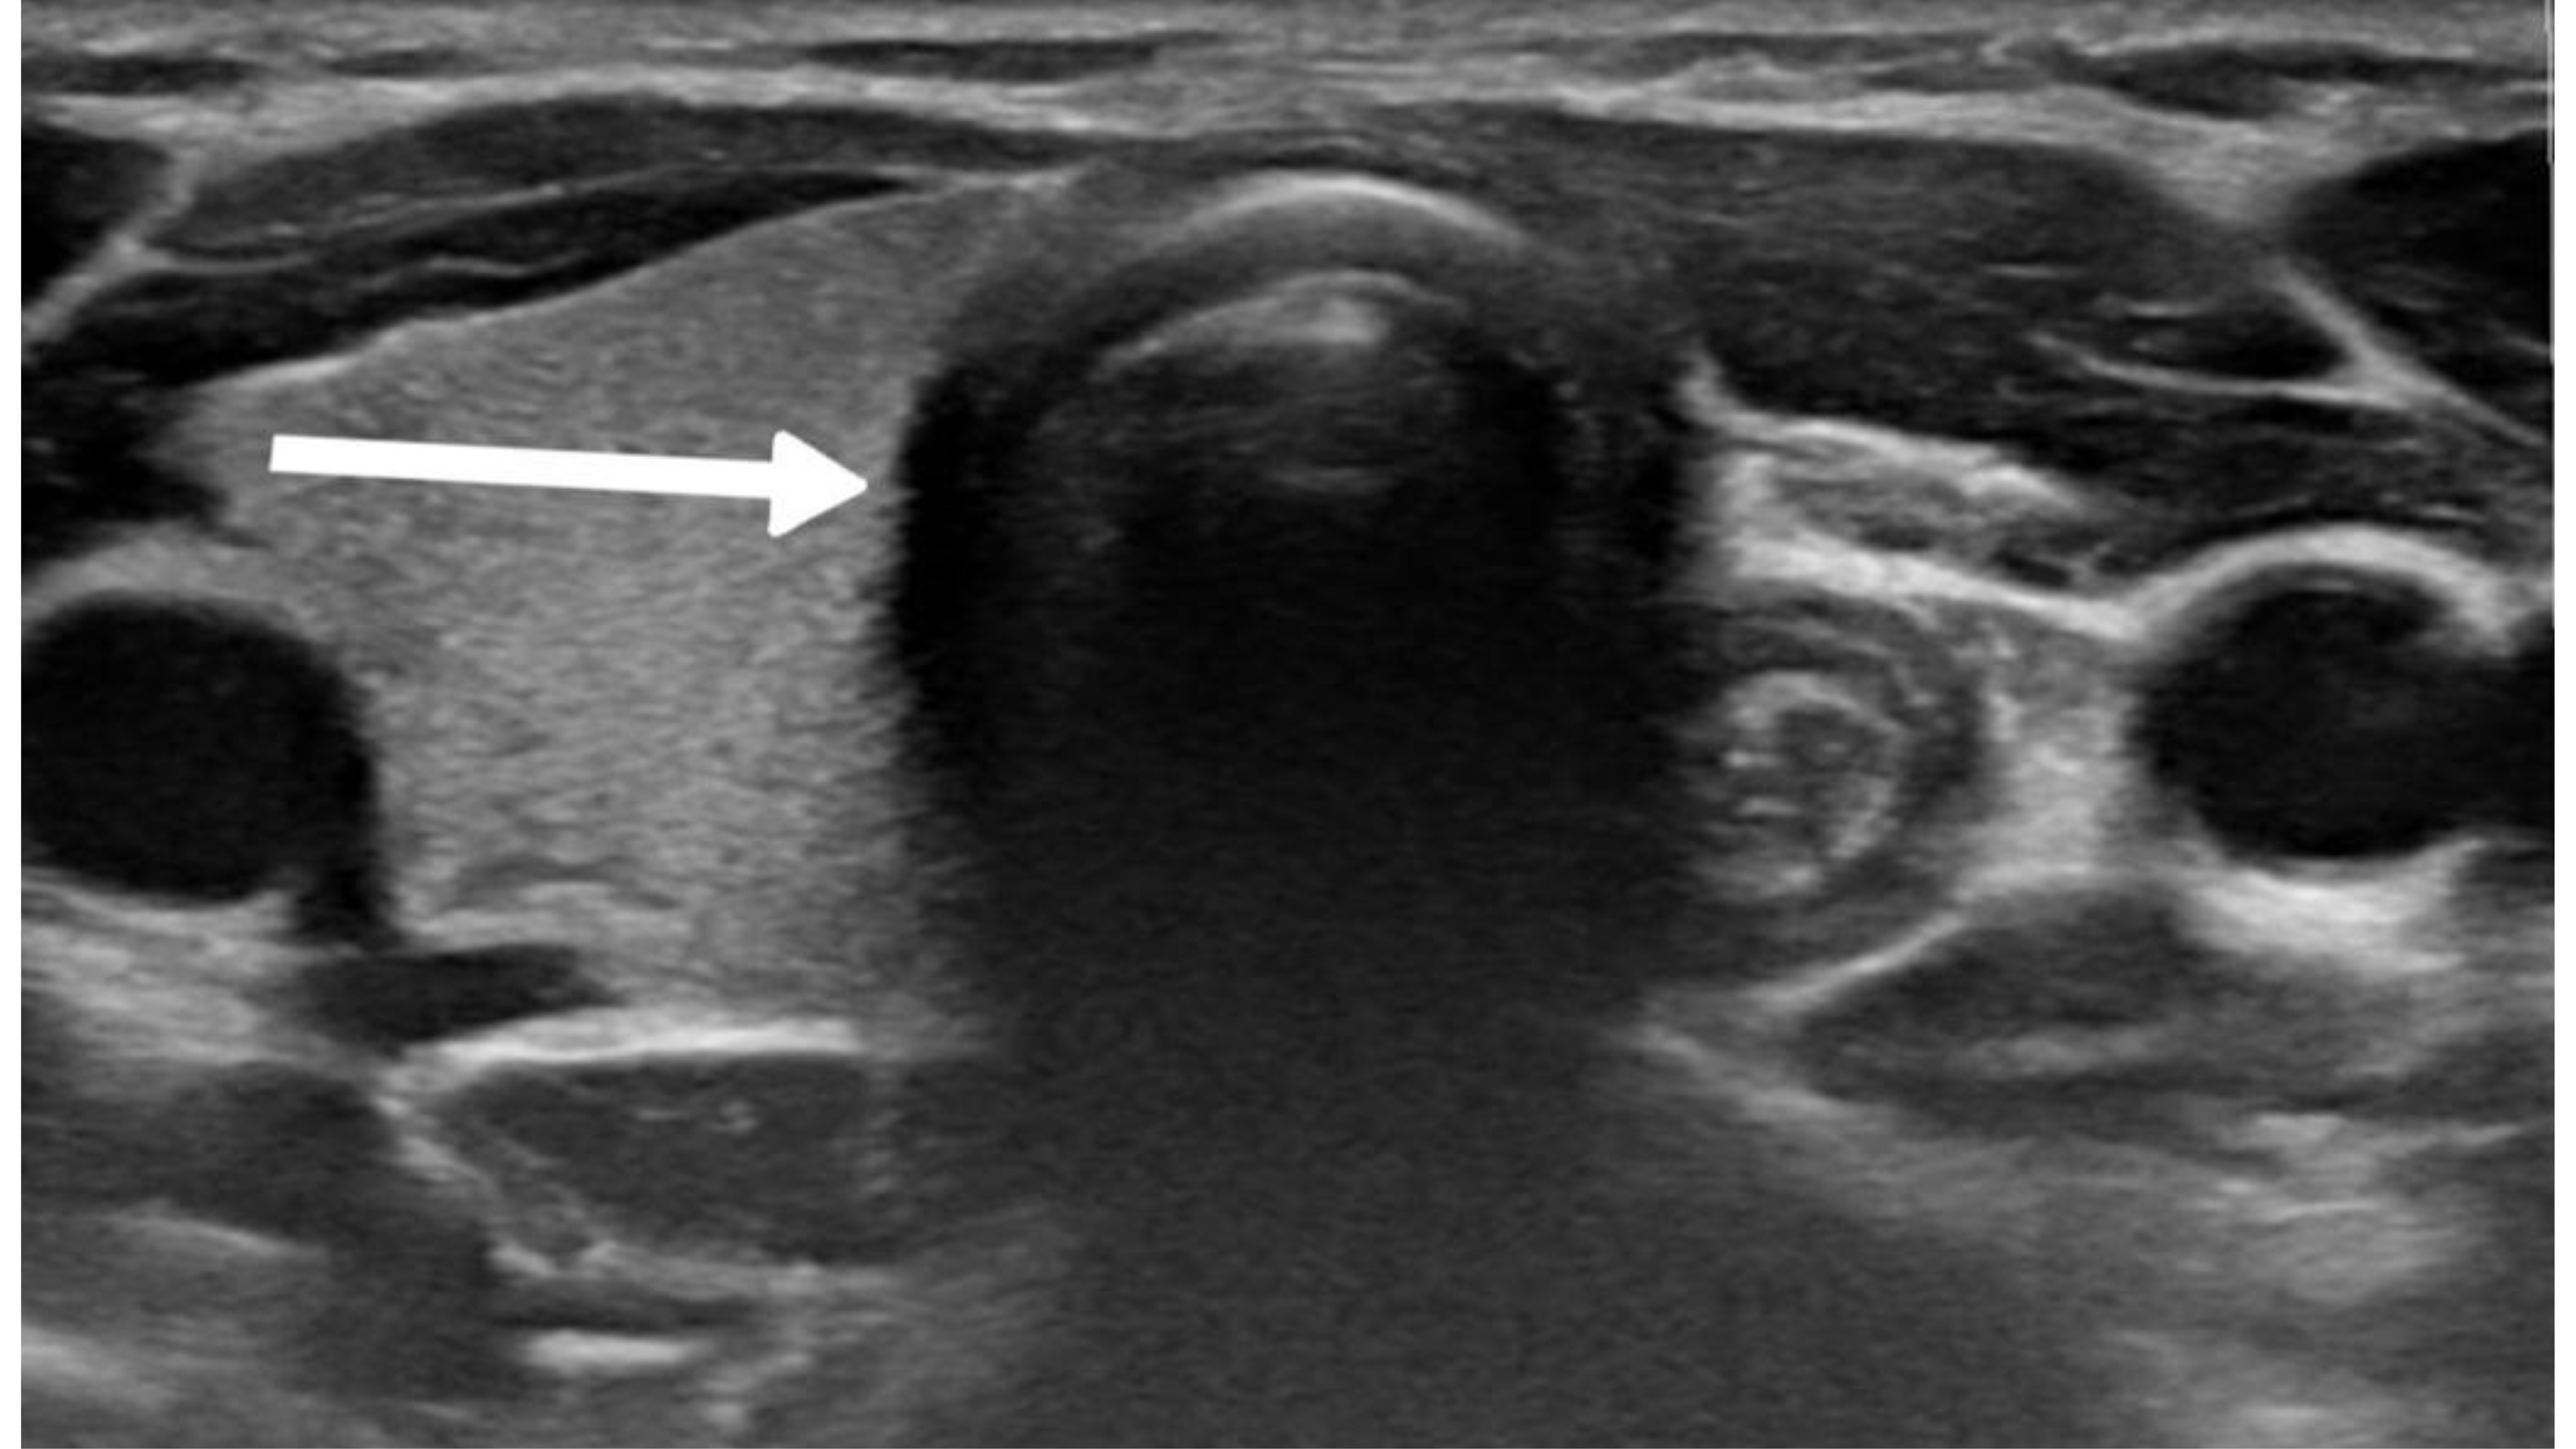

The diagnostic evaluation of most thyroid nodules typically begins with U/S, followed by fine needle aspiration (FNA). The U/S findings suggestive of HTT are well-defined, solitary, oval or round, solid hypoechoic nodules, usually without microcalcifications and displaying peri or intra-nodular vascularity. However, these features are not specific to HTT and may also occur in other thyroid lesions [7]. Recognizing the variability in U/S findings is crucial, as some studies reported an absence of malignant features. In contrast, Choi et al. found that 29% of HTT cases displayed malignant features on U/S [5,11]. In the present study, five cases were classified as mildly suspicious for malignancy, and three were considered moderately suspicious for malignancy according to the thyroid imaging reporting and data system (TI-RADS). Among the reviewed cases, malignancy was also suspected in four patients based on the U/S findings [2,3,7-10].

Thyroid function assessment revealed that the majority (7 cases ,63.6%) of patients were euthyroid (0.35-4.5µIU/mL), while two patients exhibited hyperthyroidism (<0.35 µIU/mL), and two of them had hypothyroidism (>4.5 µIU/mL). Ultrasound findings demonstrated left lobe and isthmus agenesis in eight cases (72.7%), while two cases (18.2%) exhibited isolated left lobe agenesis, and one patient exhibited isolated right lobe agenesis (9.1%) (Figures 1 and 2). The largest documented normal lobe measured 100 × 43 × 35 mm, whereas the smallest measured 15 × 6.9 × 7.9 mm. The follow-up period ranged from 4 to 48 months (Tables 1-3).